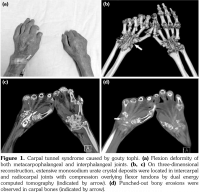

A 54-year-old male patient was admitted to our department with palmar numbness and disability for two years. He had a history of gout for 30 years but received no treatment. Physical examination revealed obvious subcutaneous tophi and thenar muscle wasting. Flexion deformity of his metacarpophalangeal and interphalangeal joints is shown in Figure 1a. Positive Tinel’s sign and Phalen’s maneuver were present. Routine laboratory test showed high level of uric acid (608 μmol/L). The electrophysiological examination revealed sensory and motoring demyelinating and axon lesions in both median nerve, especially in the right hand, which supported the diagnosis of CTS. Furthermore, DECT showed extensive monosodium urate crystals in the intercarpal and radiocarpal joints with compression overlying the flexor tendons (Figure 1b, c). We also observed punched-out bony erosions in the carpal bones (Figure 1d). These aspects indicated severe and typical CTS caused by gouty tophi, which was further confirmed by biopsy of fine-needle aspiration (Figure 2). Surgery was recommended, but the patient refused to undergo surgery and chose to receive febuxostat. Uric acid level had decreased in the next six-month follow-up with little improvement for his numbness and deformity. A written informed consent was obtained from the patient.